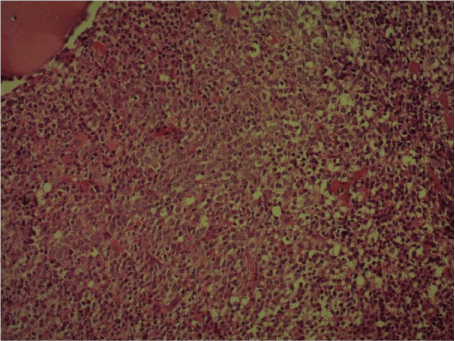

Complete blood counts objectified deep center bicytopenia (anemia at 5.6 g/dl and thrombocytopenia at 10,000/mm3). Médullogramme showed a very average wealth of marrow with few and dystrophic megakaryocytes. Bone marrow biopsy objectified bone marrow hyperplasia with signs of dysmyelopoiesis, PRCA and densification of the reticulin network can be compared with a toxic myelopathy (Figure 3). Immunohistochemistry showed a reaction marrow hyperplasia with absence of bone marrow infiltration (Figures 4 and Figure 5) and pharmacovigilance center concluded to direct toxicity of tamoxifen.

Figure 3: Bone marrow biopsy (HE x200) showing a marrow hyperplasia with dysmyélopoise signs.